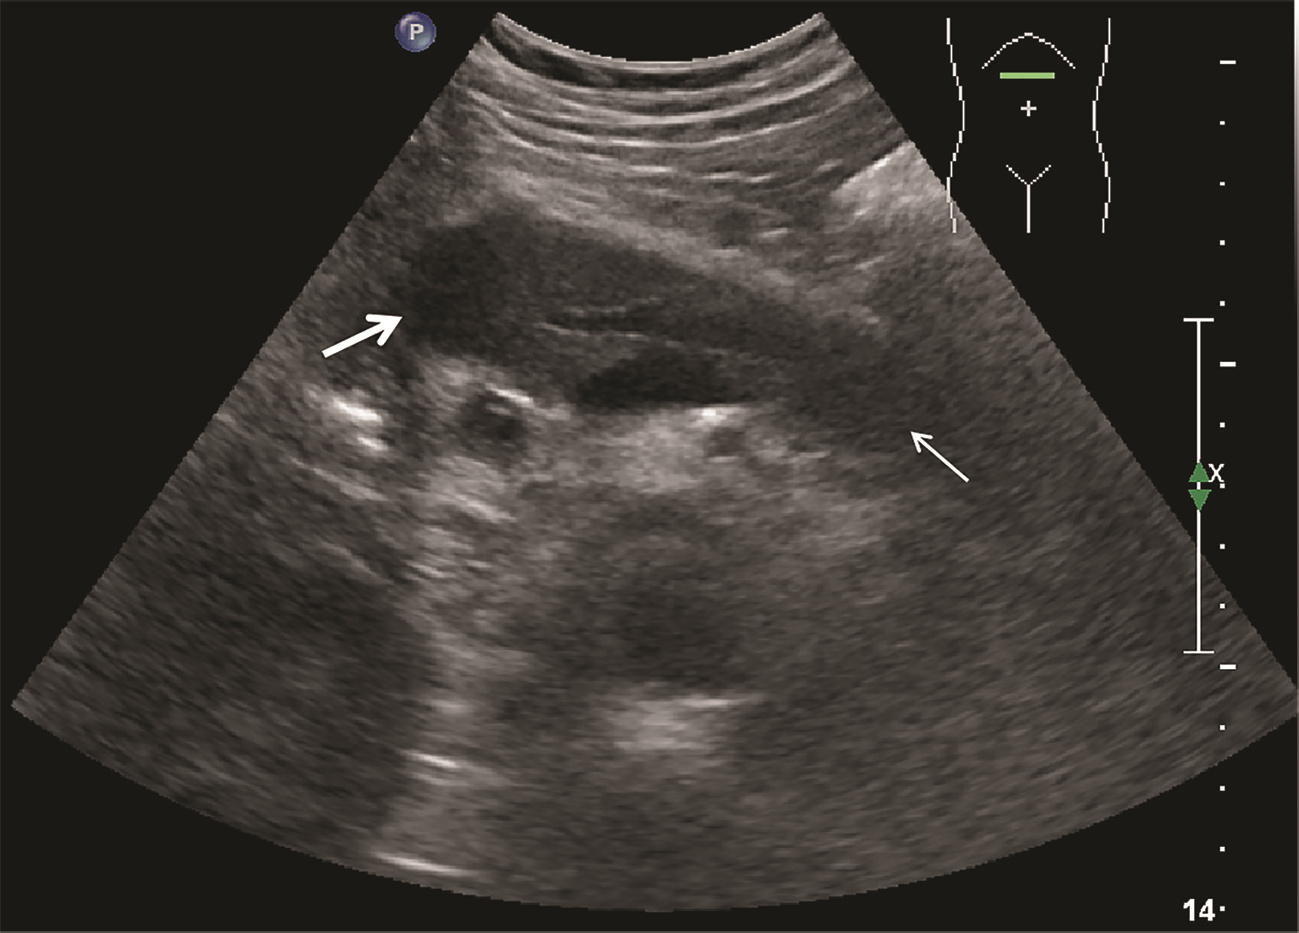

Ultrasound findings and contrast-enhanced ultrasound findings of mass-type autoimmune pancreatitis versus pancreatic ductal adenocarcinoma

Xiangliu OUYANG, Yunxia HAN, Lichun ZHENG, Yingchun ZHAO, Xinyu SHEN, Wenjun ZHANG, Yanbin WANG

2022, 38(6): 1351-1355. DOI: 10.3969/j.issn.1001-5256.2022.06.025

Abstract(1427) HTML (553) PDF (3738KB)(50)

Abstract:

Objective  To investigate the value of ultrasound and contrast-enhanced ultrasound (CEUS) in the differential diagnosis of mass-type autoimmune pancreatitis (AIP) and pancreatic ductal adenocarcinoma (PDAC).  Methods  A retrospective analysis was performed for the clinical data, ultrasound findings, and CEUS findings of 11 patients with mass-type AIP who were diagnosed in Tangshan Workers' Hospital from January 2015 to December 2020, and their characteristic manifestations were analyzed and compared with the data of 23 patients with PDCA. The chi-square test was used for comparison of categorical data between two groups.  Results  For the 11 patients with mass-type AIP, CEUS had a diagnostic accuracy of 63.64%, and all of these patients had hypoechoic single lesions; the patients with clear boundaries, regular morphology, pancreatic duct dilatation or cutoff, and blood flow signal accounted for 54.55%, 63.64%, 18.18%, and 36.36%, respectively, while in the PDCA group, such patients accounted for 30.43%, 34.78%, 78.26%, and 21.74%, respectively, and there was a significant difference in the presence or absence of pancreatic duct dilatation or cutoff between the two groups(χ2=11.089, P < 0.05), with no significant differences in the other indices (all P > 0.05). For the 11 patients with mass-type AIP, CEUS showed that 7 patients (63.64%) had hyperenhancement and 4 (36.36%) had iso-enhancement in the arterial phase, and 5 patients (45.45%) had hyperenhancement in the arterial phase and 6 (54.55%) had iso-enhancement in the venous phase; for the 23 patients with PDCA, 22 (95.65%) had hypoenhancement of lesions in both arterial and venous phases, and there were significant differences in the enhancement pattern in arterial and venous phases between the two groups (χ2=30.345 and 30.084, both P < 0.05).  Conclusion  The enhancement pattern of CEUS and the presence or absence of pancreatic duct dilatation or cutoff have a relatively high value in the differential diagnosis of mass-type AIP and PDCA.